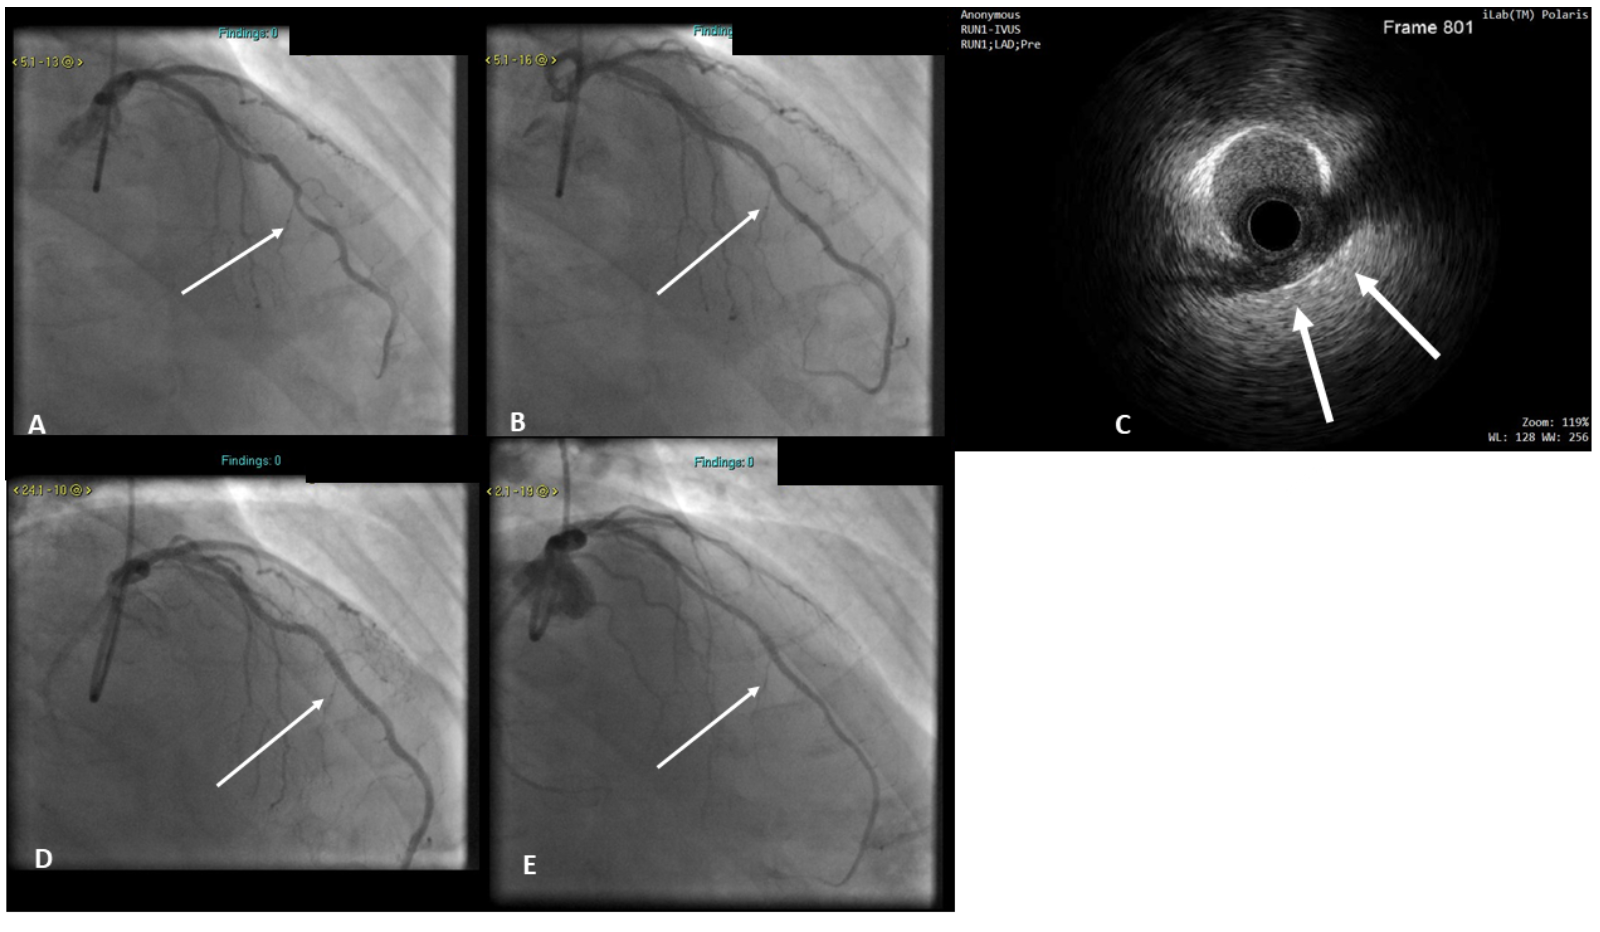

Unroofing of myocardial bridge All About Cardiovascular System and What Is A Bridge In Your Heart a myocardial bridge is a “bridge” of heart muscle that goes over, instead of under, part of an artery that brings blood to. the arteries that supply blood to the heart lie on the surface of the organ. myocardial bridging (mb) is a congenital coronary anomaly in which a segment of the epicardial coronary artery. A myocardial. What Is A Bridge In Your Heart.

Myocardial bridge bridging the differential diagnosis BMJ Case Reports What Is A Bridge In Your Heart With a myocardial bridge, part of a coronary artery dips into. A myocardial bridge (mb) occurs when a segment of a. the arteries that supply blood to the heart lie on the surface of the organ. myocardial bridging (mb) is a congenital coronary anomaly in which a segment of the epicardial coronary artery. a myocardial bridge is. What Is A Bridge In Your Heart.

PCI and Stenting for Treatment of Myocardial Muscle Bridges JIC What Is A Bridge In Your Heart myocardial bridging (mb) is a congenital coronary anomaly in which a segment of the epicardial coronary artery. a myocardial bridge is a “bridge” of heart muscle that goes over, instead of under, part of an artery that brings blood to. the arteries that supply blood to the heart lie on the surface of the organ. With a. What Is A Bridge In Your Heart.

(PDF) Myocardial bridges Overview of diagnosis and management ROGERS What Is A Bridge In Your Heart With a myocardial bridge, part of a coronary artery dips into. a myocardial bridge is a band of heart muscle that lies on top of a coronary artery, instead of underneath it. A myocardial bridge (mb) occurs when a segment of a. myocardial bridging (mb) is a congenital coronary anomaly in which a segment of the epicardial coronary. What Is A Bridge In Your Heart.